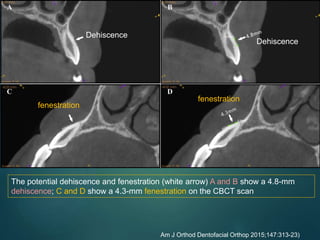

The potential dehiscence and fenestration (white arrow) A and B show a 4.8-mm

dehiscence; C and D show a 4.3-mm fenestration on the CBCT scan

Am J Orthod Dentofacial Orthop 2015;147:313-23)